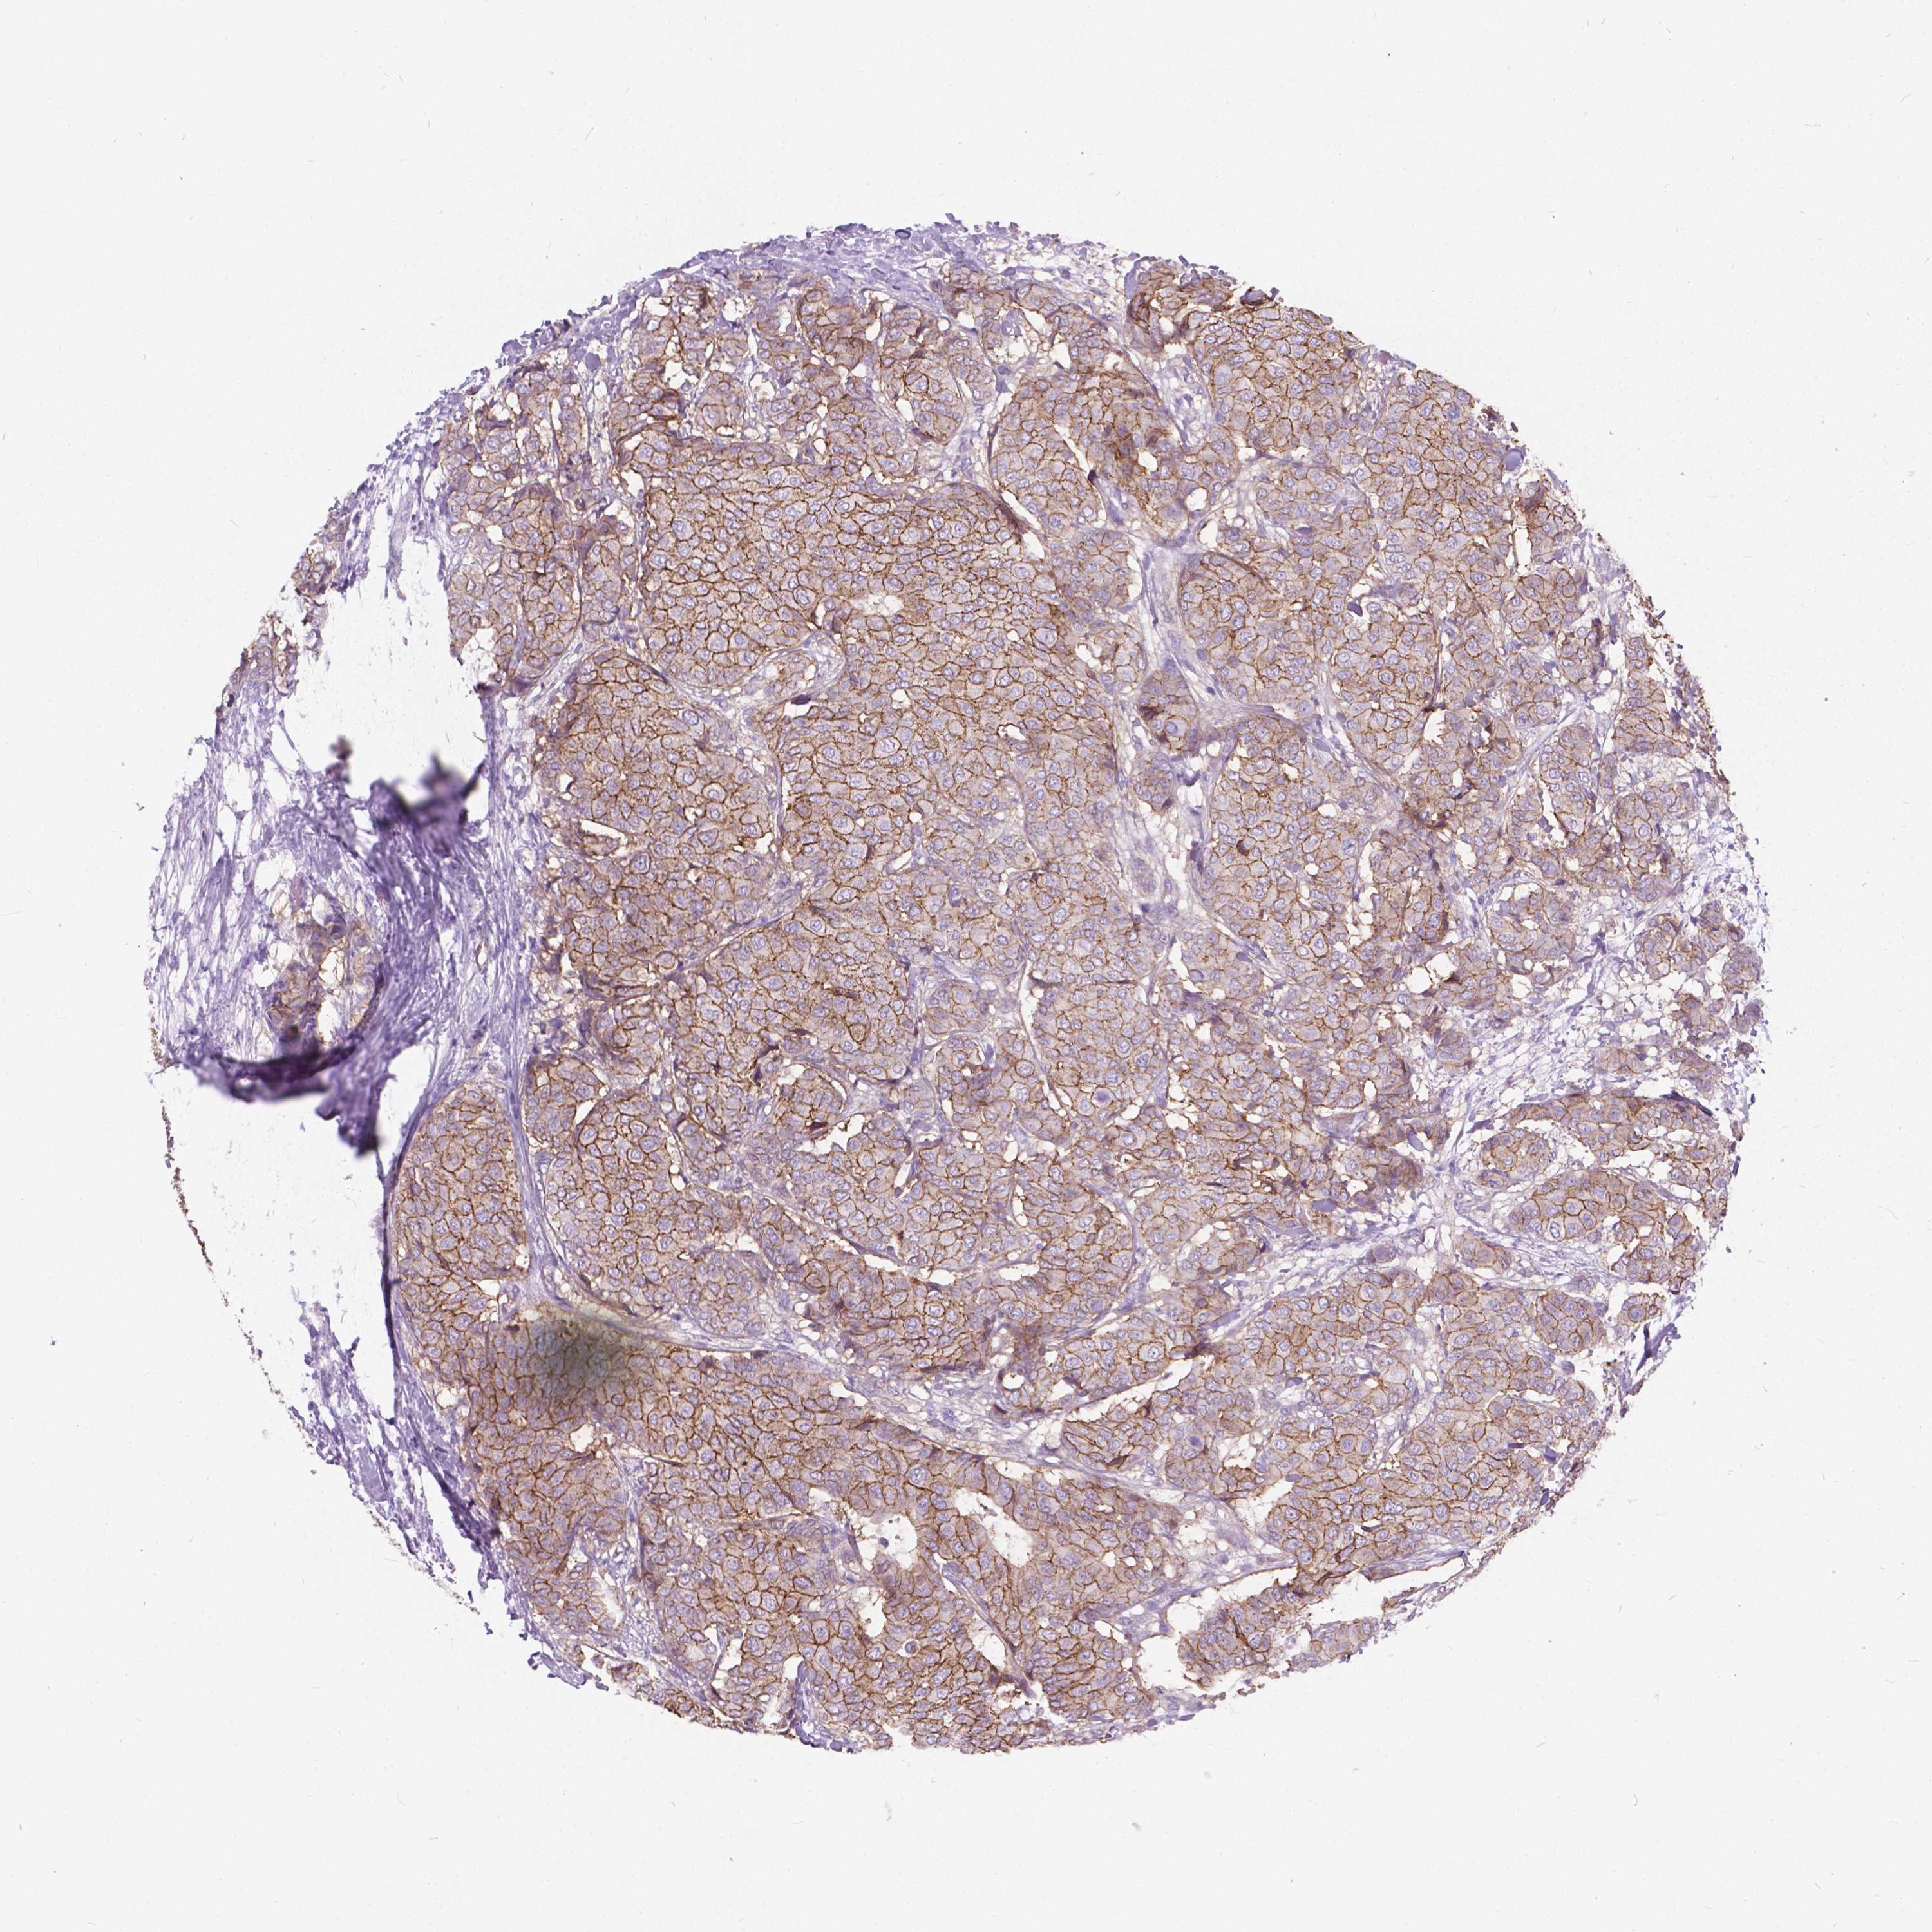

BRCA TCGA BRCA VALIDATION PROTEIN EXPRESSION

ANTIBODIES

AND

VALIDATION